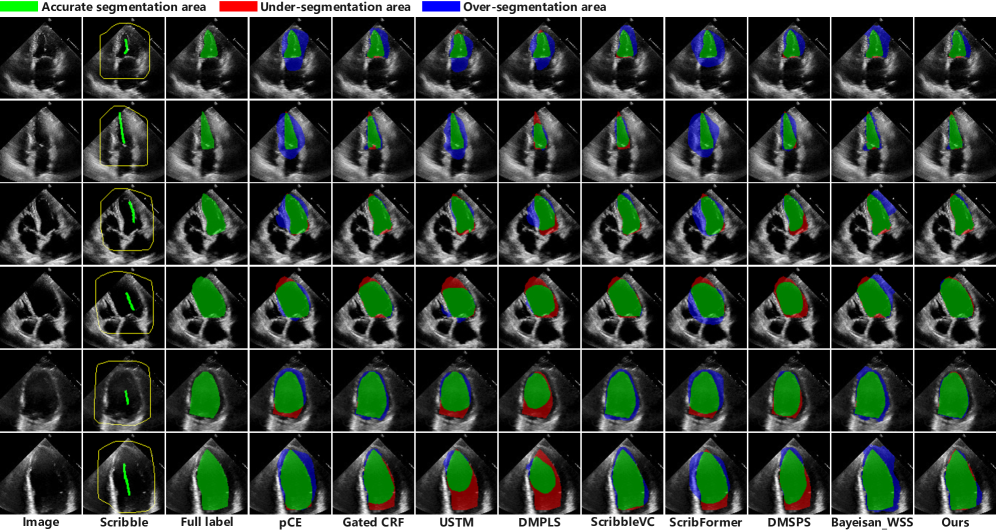

Refer to caption

Figure 7: Visualization of comparison experimental results on the BUSI dataset. The Scribble column represents scribble annotations, while the Full label column indicates full dense annotations. In scribble annotations, the yellow area represents unlabeled area. In full labels, the green area denotes the ground truth. In other segmentation results, green area indicates accurate segmentation, i.e., the overlap between the segmentation result and the ground truth. Red area represents under-segmentation (false negatives), while blue area indicate over-segmentation (false positives).

Figure 8: Visualization of comparison experimental results on the DDTI dataset. The Scribble column represents scribble annotations, while the Full label column indicates full dense annotations. Green arrows point out the missegmented regions. In scribble annotations, the yellow area represents unlabeled area. In full labels, the green area denotes the ground truth. In other segmentation results, green area indicates accurate segmentation, i.e., the overlap between the segmentation result and the ground truth. Red area represents under-segmentation (false negatives), while blue area indicate over-segmentation (false positives).

All segmentation results are visualized in Figure 7. We selected a representative set of images and their corresponding segmentation outcomes, encompassing lesions of varying morphologies and sizes, for presentation. The lesions in the first row of images were relatively small, posing challenges for some methods that tended to falsely segment similar regions as lesions, leading to false positives, while others may fail to fully segment the lesions, resulting in false negatives. In the second row, the lesion is small and blends with the background in brightness, making it difficult to discern. Most methods deviated in segmentation, while our approach accurately identified the lesion’s location. Furthermore, some lesions are large in size, posing challenges for most methods to achieve complete segmentation. Our approach succeeds by leveraging the model’s ability to comprehend global information. Additionally, the visualization results reveal that the pCE and USTM methods produce relatively more false-negative lesions in some images of this dataset, increasing the risk of missed diagnoses.

All segmentation results are visualized in Figure 8, with the selected lesions arranged from small to large in size. Some methods tended to produce false positives for small-sized lesions and false negatives for large-sized lesions. Overall, our method exhibited better performance compared to existing methods. However, upon observing the ultrasound images from the four visualization examples, it becomes evident that the lesion boundaries are unclear, making it difficult to distinguish between the lesions and normal tissues. This poses a significant challenge for weakly supervised segmentation and underscores the need for continued focus and improvement in this area of ultrasound image segmentation in the future.